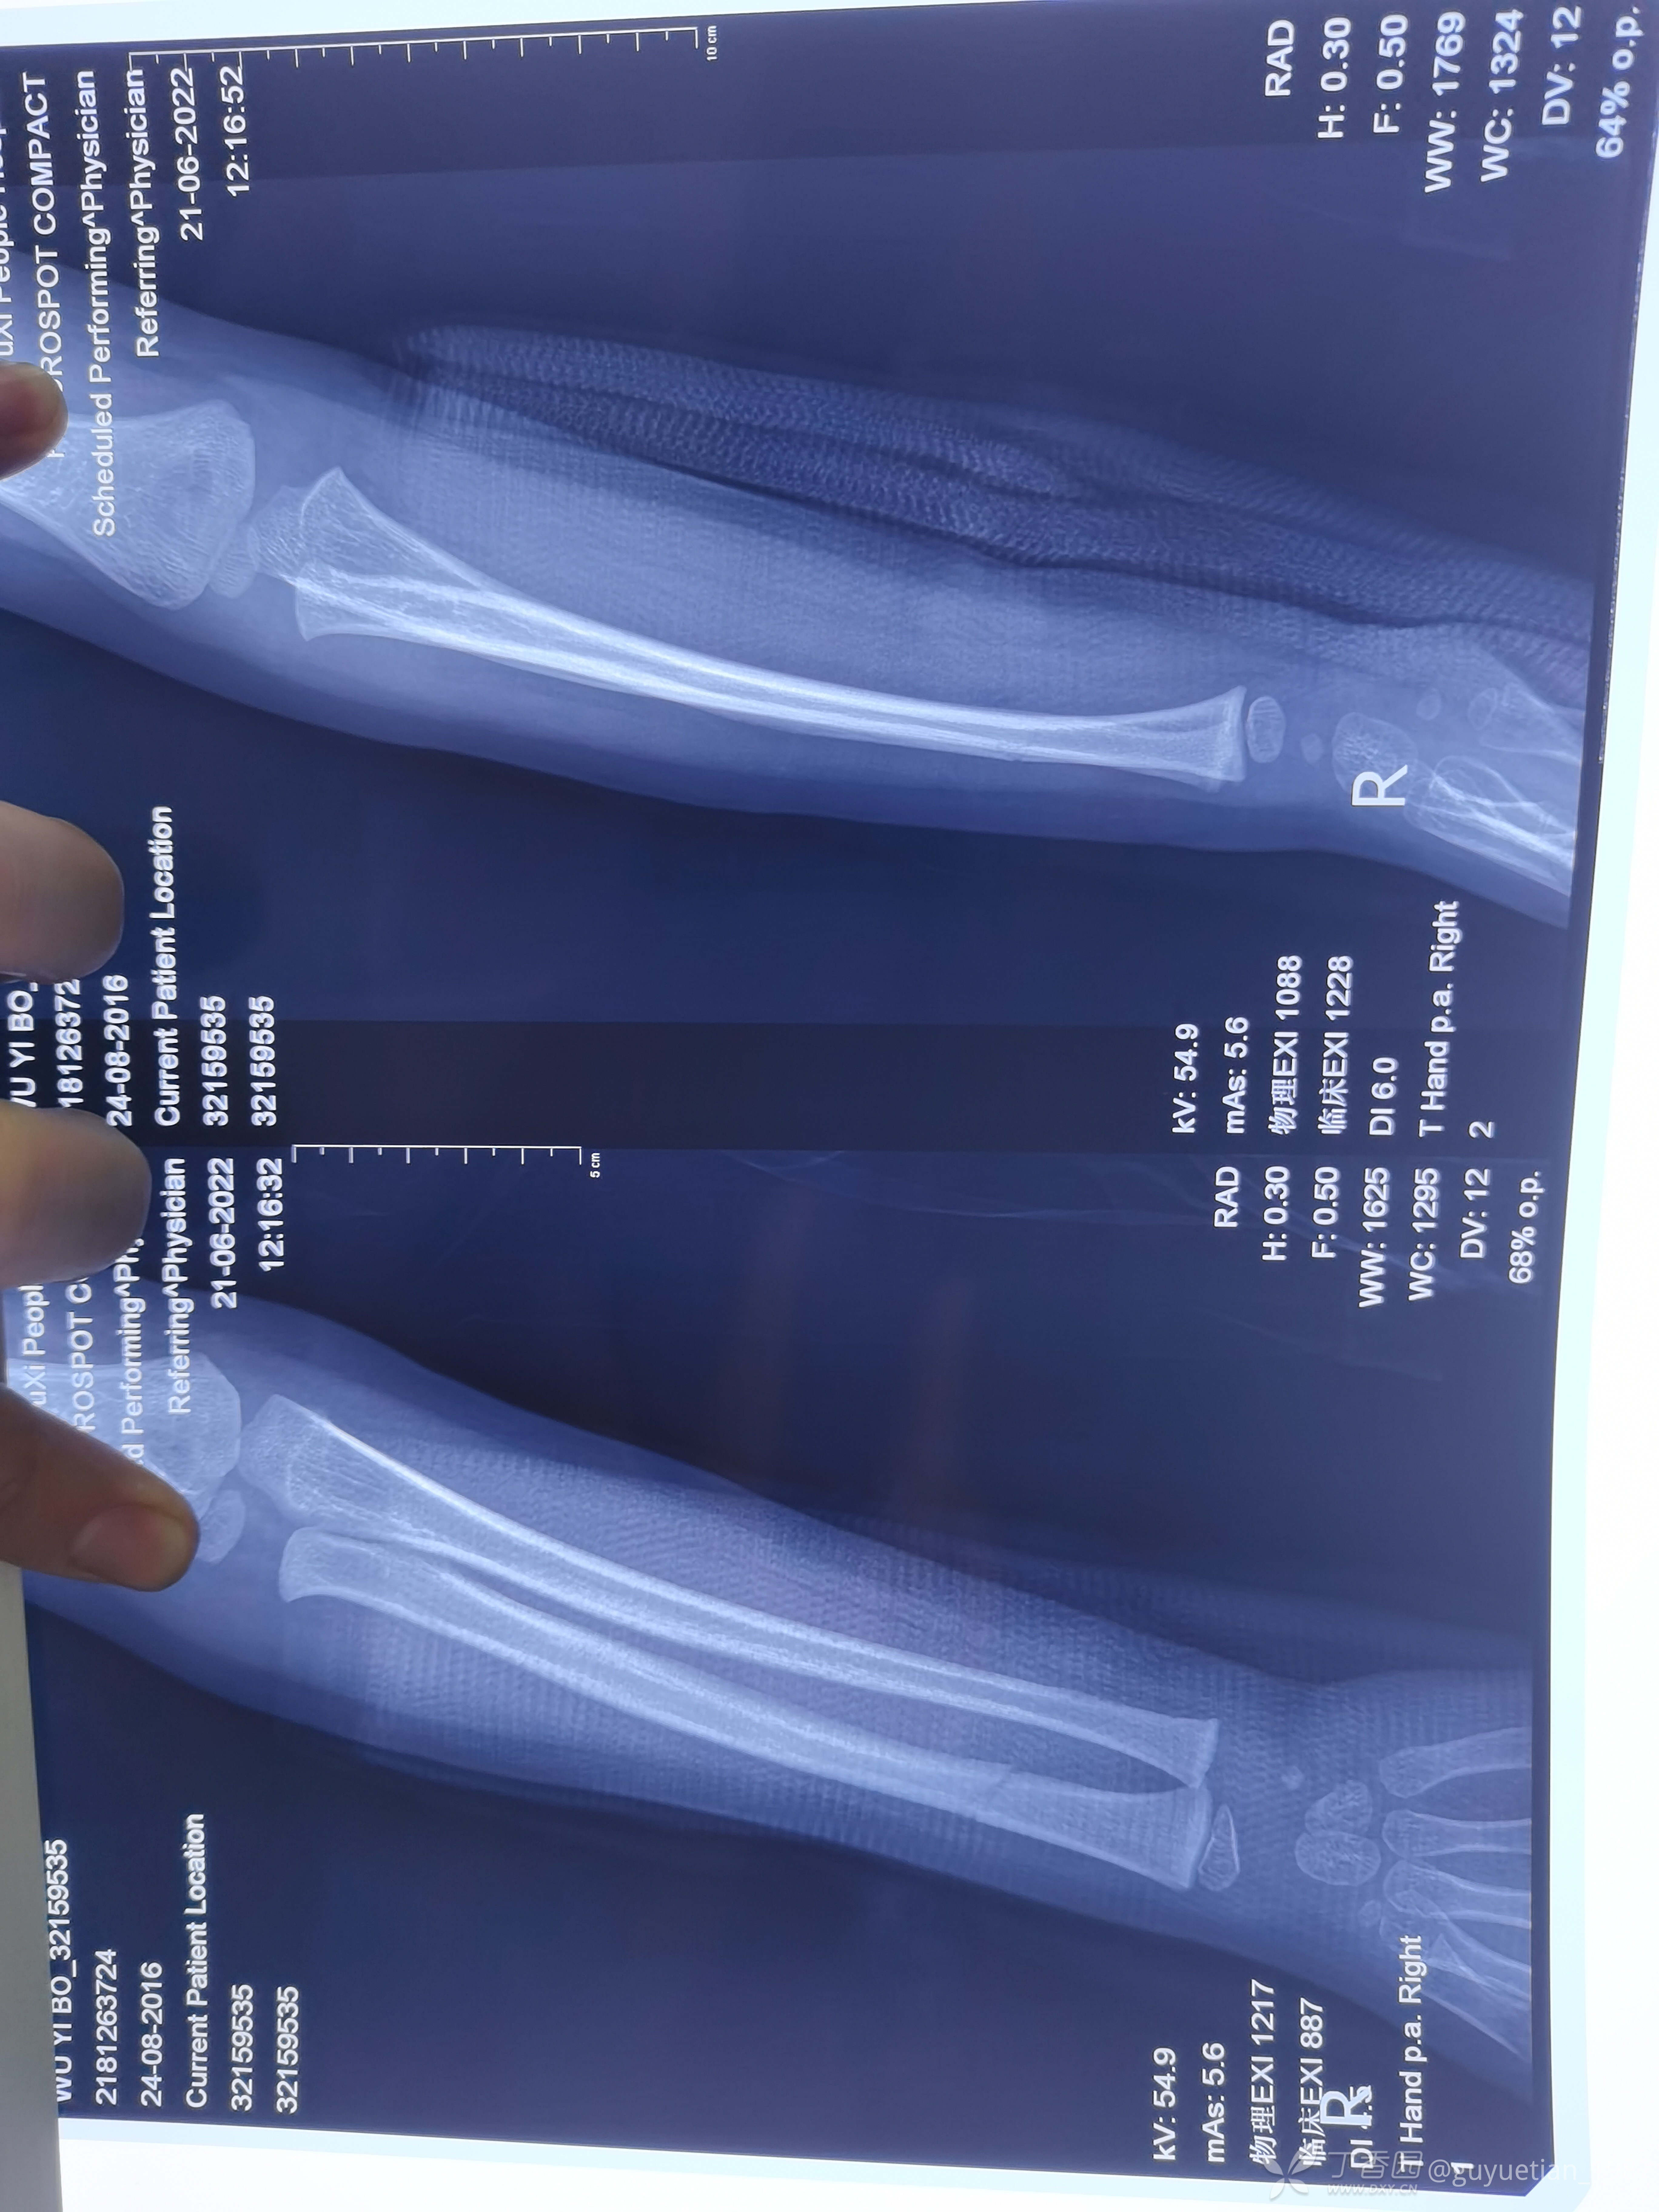

2月余复诊,基本完全塑形

信任永远是医患的基础,用心认真对待每个愿意相信你的病患。